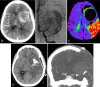

Our study aimed to evaluate the postoperative outcome of patients with unruptured giant middle cerebral artery (MCA) aneurysm revealed by intracranial hypertension associated to midline brain shift. From 2012 to 2022, among the 954 patients treated by a microsurgical procedure for an intracranial aneurysm, our study included 9 consecutive patients with giant MCA aneurysm associated to intracranial hypertension with a midline brain shift. Deep hypothermic circulatory flow reduction (DHCFR) with vascular reconstruction was performed in 4 patients and cerebral revascularization with aneurysm trapping was the therapeutic strategy in 5 patients. Early (< 7 days) and long term clinical and radiological monitoring was done. Good functional outcome was considered as mRS score ≤ 2 at 3 months. The mean age at treatment was 44 yo (ranged from 17 to 70 yo). The mean maximal diameter of the aneurysm was 49 mm (ranged from 33 to 70 mm). The mean midline brain shift was 8.6 mm (ranged from 5 to 13 mm). Distal MCA territory hypoperfusion was noted in 6 patients. Diffuse postoperative cerebral edema occurred in the 9 patients with a mean delay of 59 h and conducted to a postoperative neurological deterioration in 7 of them. Postoperative death was noted in 3 patients. Among the 6 survivors, early postoperative decompressive hemicraniotomy was required in 4 patients. Good functional outcome was noted in 4 patients. Complete aneurysm occlusion was noted in each patient at last follow-up. We suggest to discuss a systematic decompressive hemicraniotomy at the end of the surgical procedure and/or a partial temporal lobe resection at its beginning to reduce the consequences of the edema reaction and to improve the postoperative outcome of this specific subgroup of patients. A better intraoperative assessment of the blood flow might also reduce the occurrence of the reperfusion syndrome.